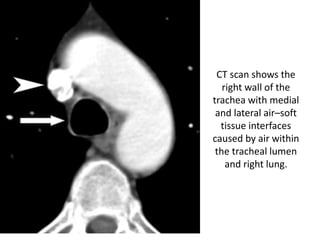

CT scan shows the

right wall of the

trachea with medial

and lateral air–soft

tissue interfaces

caused by air within

the tracheal lumen

and right lung.

CT scan showsthe right wall of the trachea with medial and lateral air–soft tissue interfaces caused by air within the tracheal lumen and right lung.